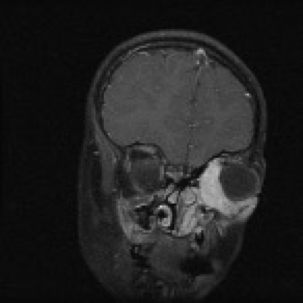

RhabdomyosarcomaHead and Neck

What does this refer to

Cranial Nerve Palsies

Hearing Loss

Chronic aural or sinus drainage

Image shows PARAMENINGEAL

Physical examRhabdomyosarcoma – Head and Neck